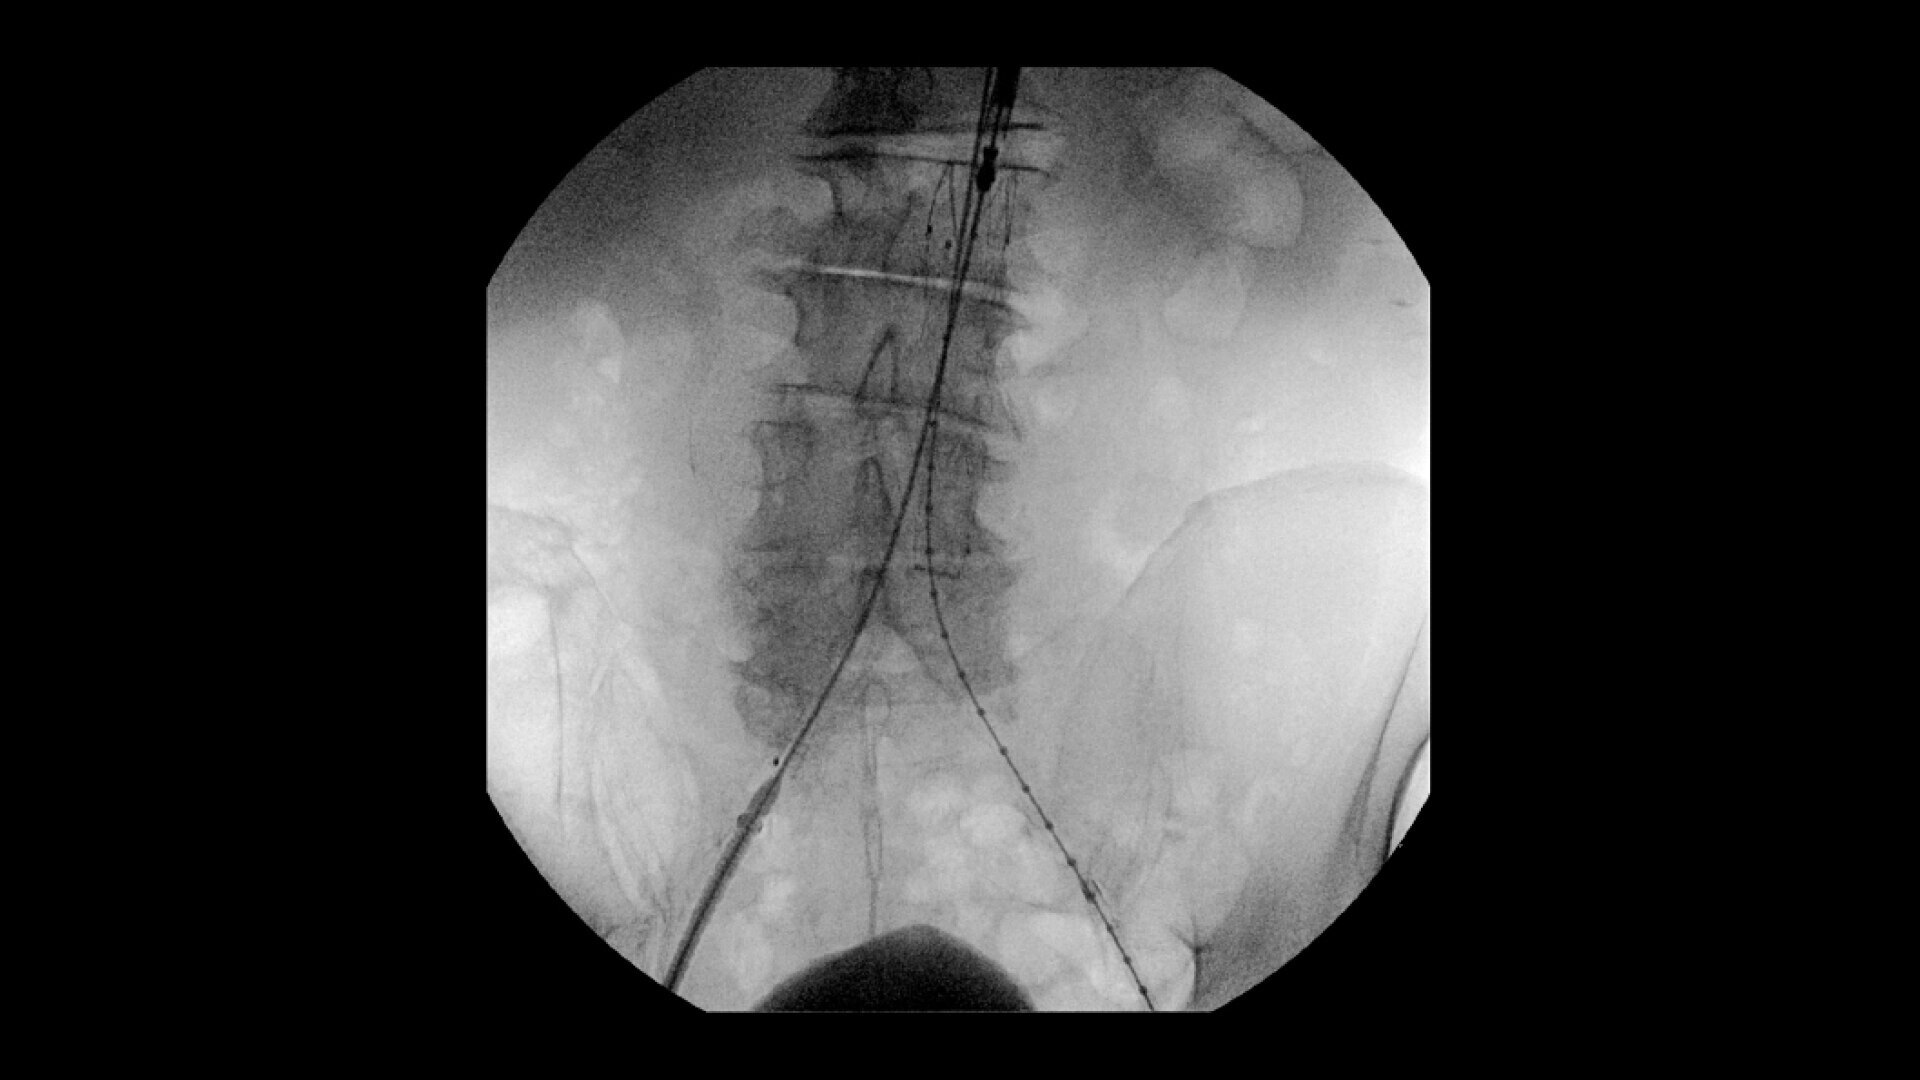

OEC C-arms are used by interventionalists and surgeons to obtain vascular imaging during peripheral to contrast run-off procedures. Superb resolution, even in the presence of motion, enables easy identification of anatomical landmarks and the extremity of the catheter, even as catheter tip moves.

Perform a full leg Bolus Chase in one contrast run with a Preset Profile that includes Motion Tolerant Subtraction, that dynamically adjusts image quality based on presence of motion.

During contrast run-off procedures, easily select contrast type with positive (e.g. Iodine) or negative (e.g. Carbon Dioxide) during subtraction. The OEC Elite CFD cardiovascular package also includes Roadmapping.

To see vessel stenosis or tips of guidewires, Live Zoom up to 4X during a fluoro or Cine without the additional dose of Mag modes or resulting X-ray tube heat buildup.

Conveniently plan procedures with comprehensive imaging tools to measure percent stenosis, distance, or angles, annotate and draw on images.